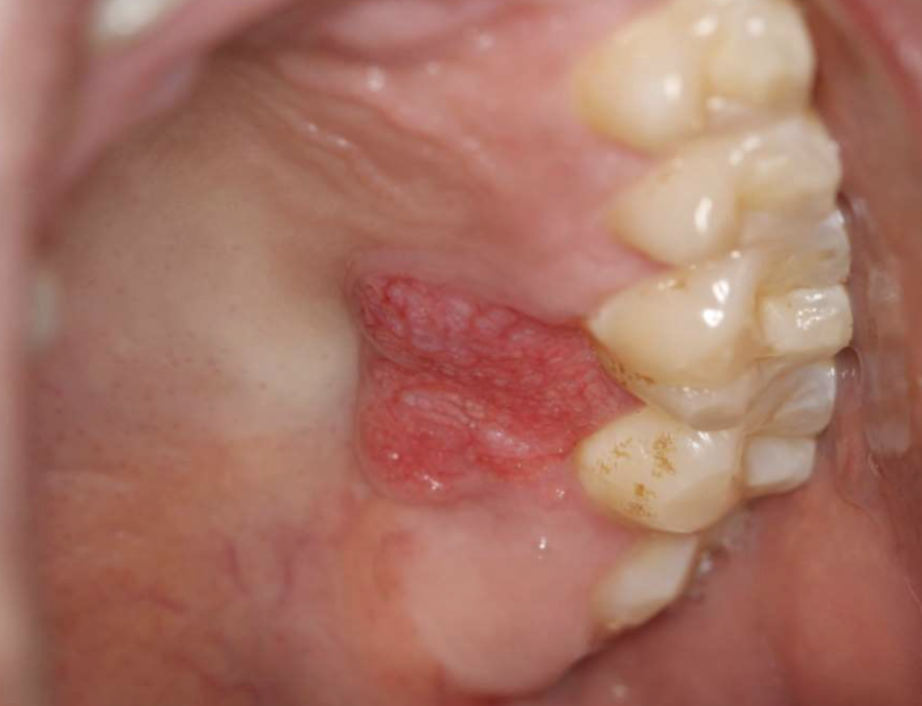

what is this

verruciform xanthoma